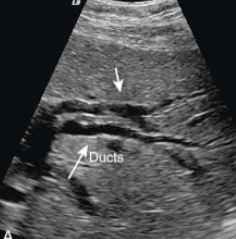

US finding

- 담낭관 또는 담낭 경부에 결석이 확인된다.

- 총간관(CHD) 또는 담낭관(cystic duct)의 확장소견이 보인다.

- 간내외 담관의 확장이 관찰된다.